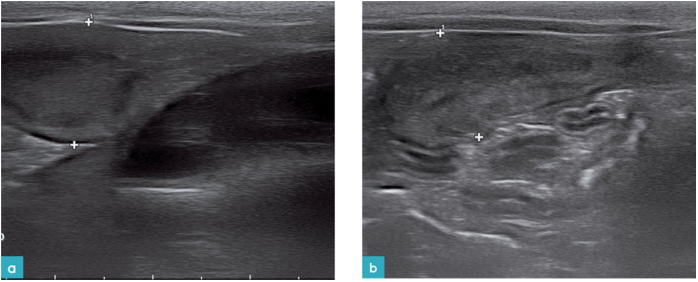

随着大脑左右半球的发育,在妊娠期第27-28天左右可见头部内容物表现为具有对称性、回声略高的影像,无回声部分减少。同一时期,胎儿心脏、肝脏、胃已清晰可见,胎儿的整体形态也与出生时相近(图8)。

猫的子宫复旧约需要24天。整个子宫复旧过程中,子宫壁的厚度下降及腔内的液体量逐渐减少,子宫也越来越不可见(图9)。